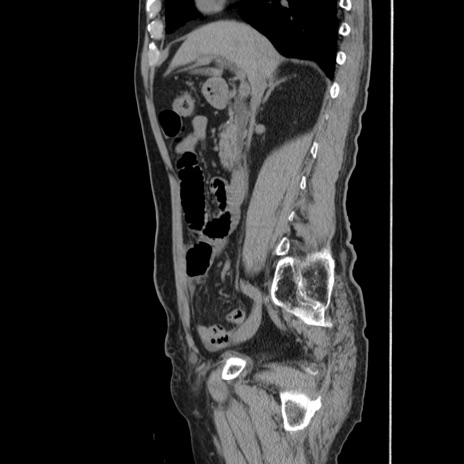

症例24(矢状断像)

【症例】80歳代男性

【主訴】左側腹部痛、嘔吐

【現病歴】本日早朝より左腹部に痛みあり。昼頃嘔吐認めたため、救急要請。

【既往歴】直腸癌(Mile手術)、胆摘

【身体所見】意識清明、BT 35.9℃、BP 221/93mmHg、SpO2 97%(RA) 、腹部:左ストーマ周囲に限局性の腹部膨隆あり。 膨隆部自発痛・圧痛あり・軟。

【データ】WBC 7700、CRP 0.09